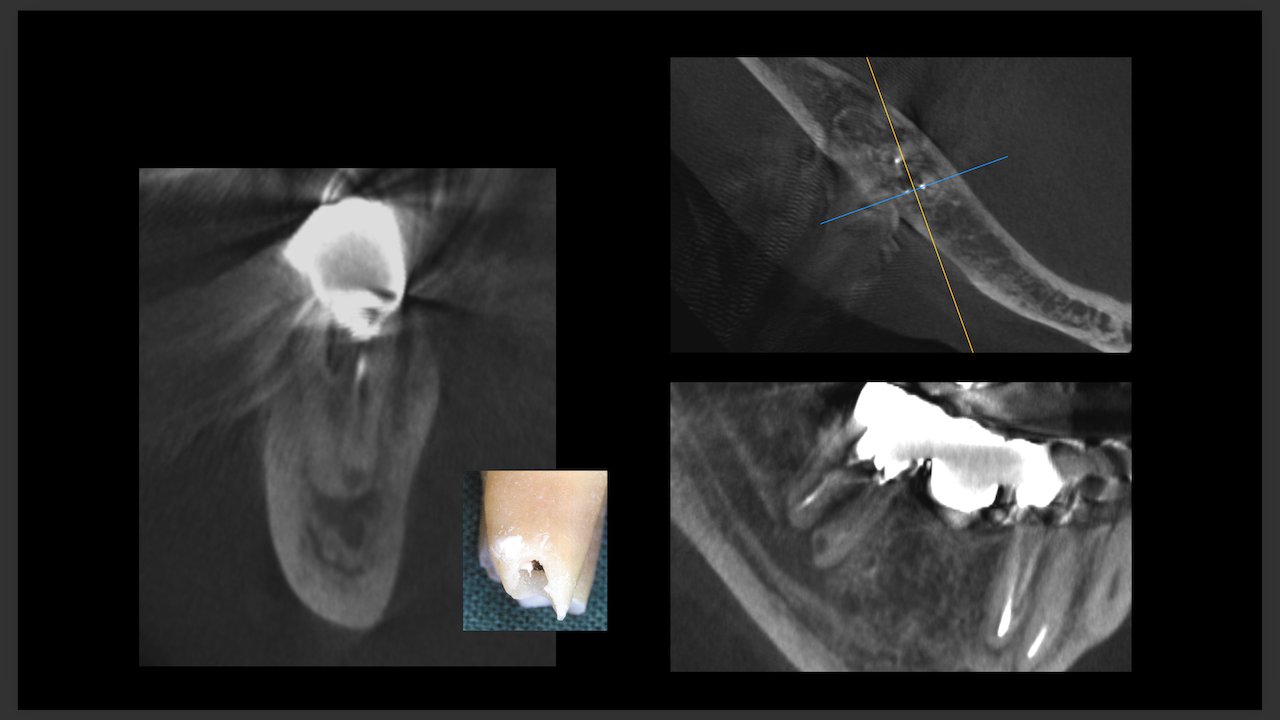

もう1ケースが以下だ。

#7がCold testに無反応である。

故に、#7,8の非外科的根管治療を行うことになった。

が、#8のメタルコアは外しにくいだろう。

CBCTでは2本とも口蓋側の皮質骨が消失している。

という絶望的な状況である。

が、

術前にその予後を患者さんに説明し、

治療へ移行した。

その結果、

ここから4ヶ月が経過すると…

臨床症状も皮質骨も大きく治癒している。

1年後の予後が気になるところであるが、すごくよくマネージメントできているだろう。